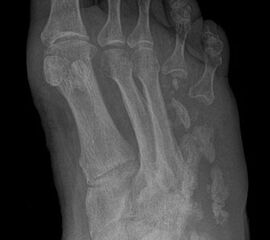

Amputationen an den Kleinzehenstrahlen

Amputation innerhalb der Kleinzehe

Eitrig-infiziertes Ulkus an der Spitze der 2. Zehe als Indikation zur Endgliedamputation.

Abbildung 13

Indikationen:

Chronisches Ulkus mit Infektion (Abb. 13).